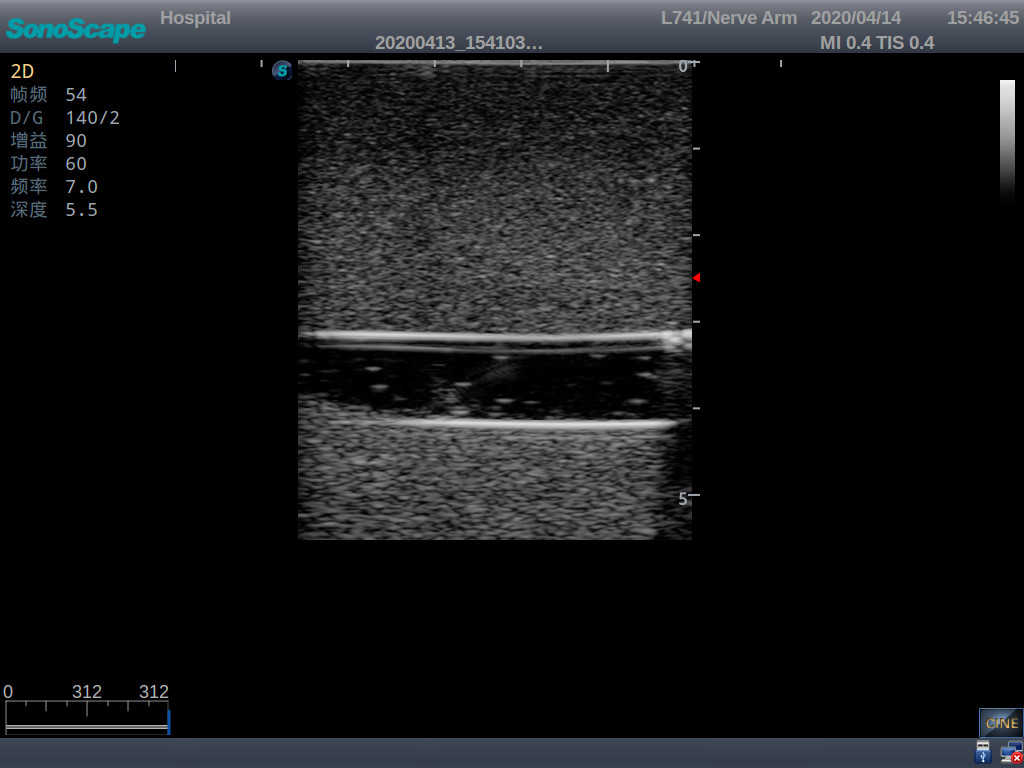

Product size(mm) 700×500×160

It is a model covering up from lobulus auriculae plane to the umbilical plane, and it has anatomical structures like clavicle, rib, sternocleidomastoid, jugular vein and basilic vein.

1)   Made of high molecular polymer ultrasound material, close to the real skin

2)   It can be used by real ultrasound machines

3)   Clear and real images of the tissues and organs (basilic vein and superior vena cava)